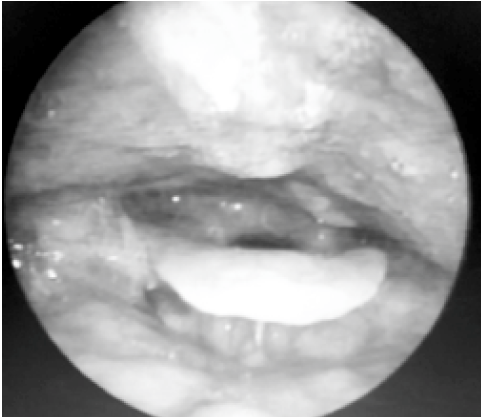

Background : Vocal fold nodules are small bilateral swellings (less than 3 mm in diameter) that develop on the free edge of the vocal fold at approximately the mid-membranous portion. It presents as hoarseness, vocal fatigue and breathiness. This study was carried out in a tertiary care hospital to study the management of vocal nodules in patients diagnosed with vocal nodules in the Otorhinolaryngology department.

Aims and Objective: To study the role of voice therapy in the management of vocal nodules.

Method : This prospective study was conducted in the Otorhinolaryngology department of a tertiary care hospital from 1st June 2023 to 29th February 2024 on patients diagnosed with vocal nodules in the Department of Otorhinolaryngology.

Results: On laryngoscopic evaluation, after 6 weeks of voice therapy, 12 out of 14 patients (86%) showed resolution of the nodule and the rest 2 (14 %) patients had persistent nodules. Those 12 patients also showed an improvement in VHI score from 14.5 at the time of diagnosis to 1.5 at the end of 6 weeks after voice therapy.

Conclusion: In our study it has been found that combination of voice therapy, vocal hygiene, and medication management is a successful treatment regimen of vocal nodules. Also the patient’s gave feedback that their voice better quality improved. Rigid video-directed laryngoscopy revealed that while the nodules had shrunk in size and the amount of edema had subsided, they had not entirely resolved.

Keywords: Voice therapy, vocal nodule, voice change.